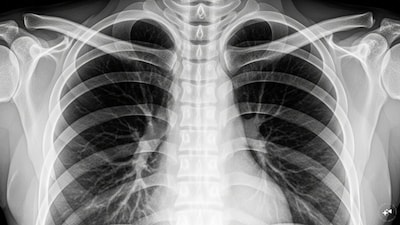

- •एक साल के बच्चे भरत को बादाम का टुकड़ा निगलने के बाद सात दिनों तक लगातार खांसी, बुखार और सांस लेने में तकलीफ हुई.

- •सीटी स्कैन से बच्चे के बाएं फेफड़े में बादाम का टुकड़ा फंसा होने की पुष्टि हुई, जिसके बाद आपातकालीन ब्रोंकोस्कोपी की गई.